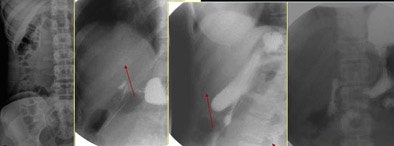

![]() |

| An upper GI barium study was performed on a 16-year-old girl who had swallowed a hat pin. By plain films (above), the physicians could not determine which part of the gastrointestinal tract it was lodged in. The patient was given barium and rotated under fluoroscopic control to make sure the pin was in the duodenum and accessible to endoscopic removal. Review with LFH (below) made it clear the pin was in the duodenum, and endoscopy proved the diagnosis correct. |